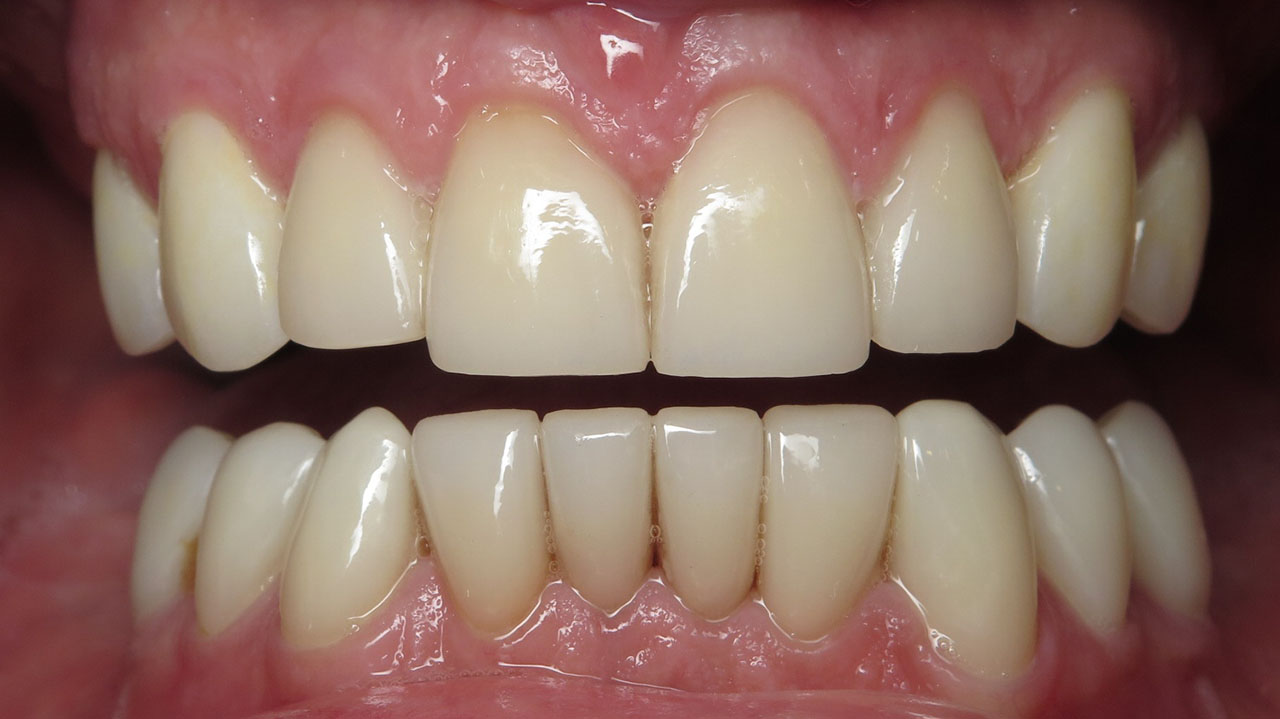

The patient regained a stable bite and preserved his remaining natural teeth. Implant replacement of missing molars was discussed but postponed for financial reasons.

Treatment was completed in stages. The upper teeth were restored first with all-ceramic crowns to rebuild the bite. After a pause to allow the patient time for physical and financial recovery, treatment continued with restoration of the lower teeth.

The result is a stable bite that protects the remaining teeth and restores comfortable chewing.